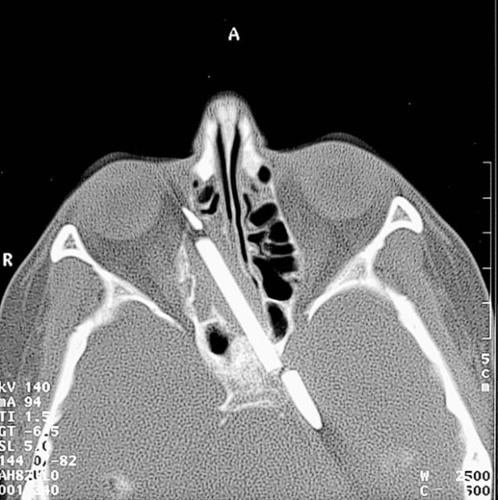

BERLIN — A woman who had a pencil lodged in her head for 55 years after a childhood accident has finally had most of it removed, which should end her chronic headaches and nosebleeds, her doctor said Tuesday.

Margaret Wegner was 4 when she fell while carrying the 3.15-inch pencil; it went through her cheek and into her brain.

At the time, the technology did not exist to safely remove the pencil, so Wegner, now 59, had to live with it — and the ensuing chronic headaches, nosebleeds and loss of sense of smell — for the next 5 1/2 decades.

But on Friday, Dr. Hans Behrbohm, an ear, nose and throat specialist at Berlin's Park-Klinik Weissensee, was able to identify the exact location of the pencil so that he could determine the risks of removing it, and then took most of it out.